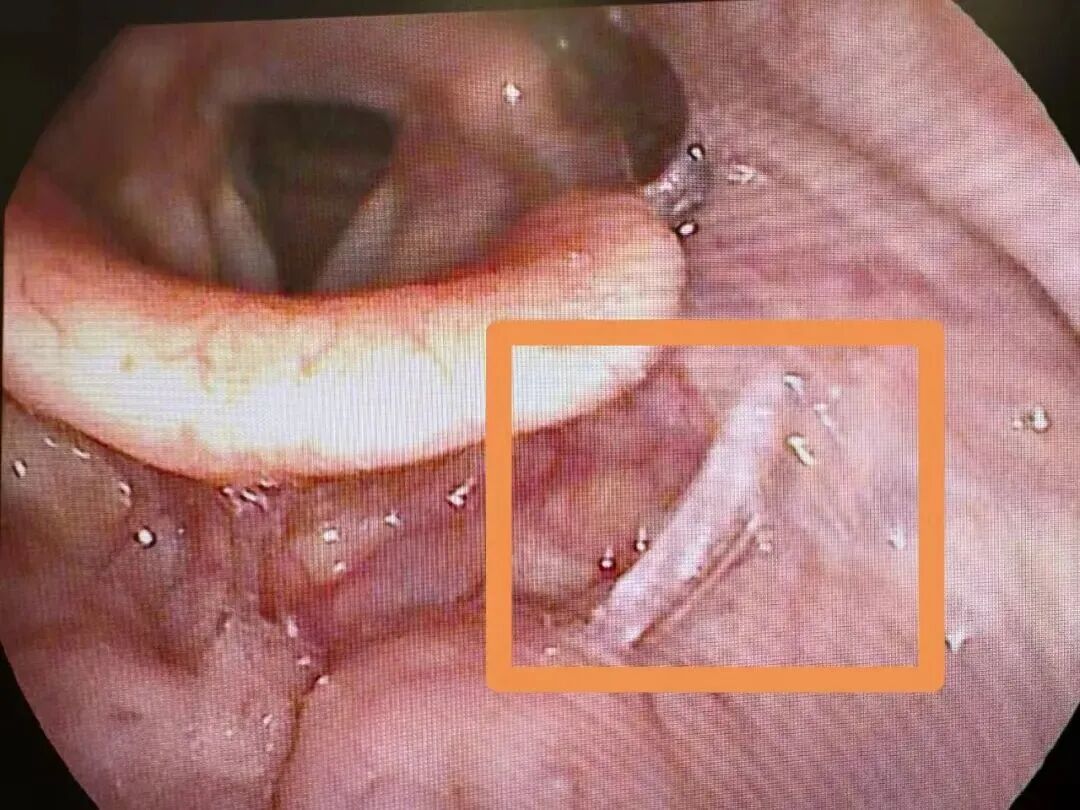

“醫生,快救救孩子!”近日,一名4歲幼童小文(化名)被媽媽抱著沖進了蕭山區第一人民醫院耳鼻咽喉科急診診室。只見孩子的小臉憋得通紅,不停作嘔,情況十分危急。當班的郭永康副主任醫師迅速檢查,發現小文喉間竟卡著一塊碎骨。

萬幸的是,經過郭醫生的專業處置,成功將帶血的碎骨取出,小文終于能大口呼吸了,此時的他睫毛上還掛著未干的眼淚。“湯飯里的碎骨、魚刺一定要仔細挑,孩子吃飯千萬要小心!”郭醫生指著托盤里的碎骨,向小文媽媽鄭重叮囑道。

郭醫生介紹,因誤食碎骨、魚刺等導致喉部異物,進而引發不適甚至損傷的情況,在臨床上并不少見,尤其在食用“湯泡飯”時更容易發生。近一個月,區一醫院急診接診的相關病人就有800余例。其中,大部分患者的異物位置較淺,可通過異物鉗直接取出,但也不乏因異物卡得深、形態特殊,需借助軟鏡才能取出的案例,不僅治療周期長,患者承受的痛苦也更多。